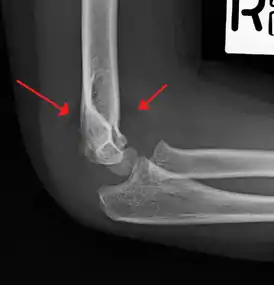

On lateral view of the elbow, there are five radiological features should be looked for: tear drop sign, anterior humeral line, coronoid line, fish-tail sign, and fat pad sign/sail sign (anterior and posterior).[3][8]

Fat pad sign/sail sign - A non-displaced fracture can be difficult to identify and a fracture line may not be visible on the X-rays. However, the presence of a joint effusion is helpful in identifying a non-displaced fracture. Bleeding from the fracture expands the joint capsule and is visualized on the lateral view as a darker area anteriorly and posteriorly, and is known as the sail sign.[8]

Fish-tail sign - The distal fragment is rotated away from the proximal fragment, thus the sharp ends of the proximal fragment looks like a shape of a fish-tail.[8]